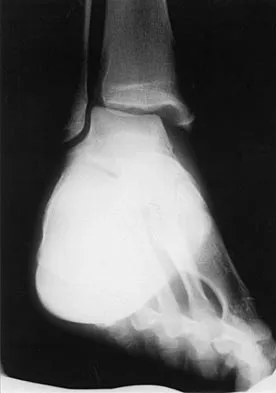

A soccer player who sustained a twisting injury to the right ankle while making a cut is unable to bear weight and has diffuse tenderness over the anterior and lateral aspects of the ankle. Examination also shows a positive squeeze test. Plain radiographs and a stress radiograph are shown in Figures 26a through 26c. Radiographs of the leg and knee are normal. What is the most appropriate management?

Explanation

The mechanism of injury, physical examination, and radiographs indicate a "high" ankle sprain with disruption of the distal tibiofibular ligaments and interosseous membrane. These injuries typically involve pronation and external rotation forces. In addition, recovery is significantly delayed, often requiring 6 to 8 weeks to heal. Radiographs obtained months after recovery often show calcification within the distal syndesmosis, which is not typically symptomatic. This patient has gross instability, resulting in a high incidence of chronic diastasis and subluxation leading to impaired function. Treatment should consist of reduction and stabilization with a transsyndesmotic screw because this injury demonstrates a widened syndesmosis. Boytim MJ, Fisher DA, Neumann L: Syndesmotic ankle sprains. Am J Sports Med 1991;19:294-298.